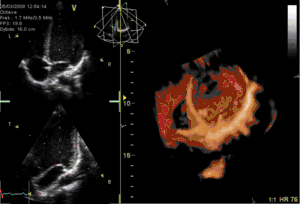

Medical imaging

- Computed tomography

- Magnetic resonance imaging

- Medical ultrasonography

- Radiology

- Tomograph, device and method for non-destructive analysis of multiple measurements done on a geometric object, for producing 2- or 3-dimensional images, representing the inner structure of that geometric object.